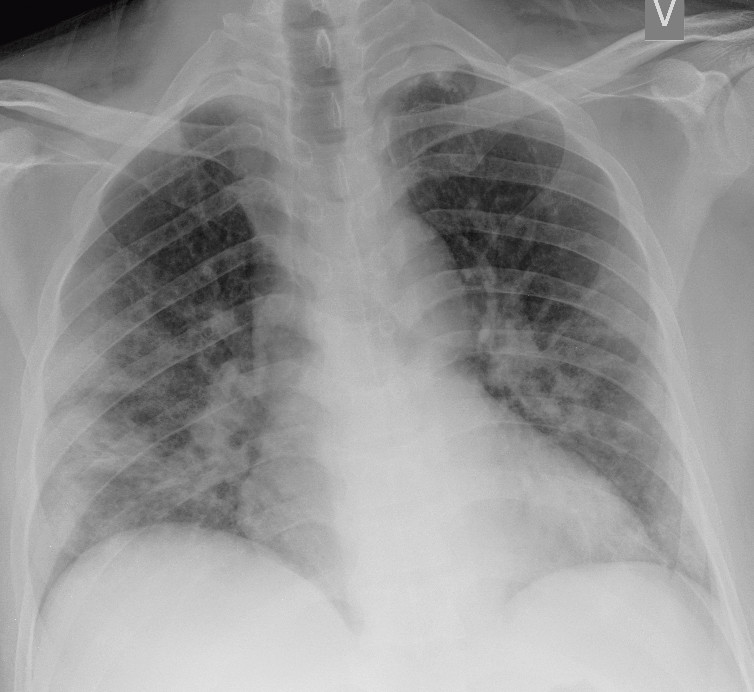

I et materiale fra Hongkong hadde 69 % funn på røntgen thorax før behandling (baseline), men 9 % hadde funn på røntgen thorax før positiv PCR (14). Sensitiviteten for røntgen thorax var 69 % og for PCR 91 %. Vanligste røntgenfunn var bilateral konsolidering og mattglassfortetninger med perifer og kaudal distribusjon. Forandringene var mest uttalt 10–12 dager etter symptomdebut. Figur 1 og figur 2 viser typiske funn på røntgen thorax ved covid-19.

Pasienter med moderate symptomer skal utredes med bildediagnostikk i tråd med rutiner for luftveissykdom. Røntgen thorax anbefales imidlertid ikke som primær modalitet for spesifikk diagnostikk av covid-19, fordi et normalt røntgenbilde ikke utelukker sykdommen og fordi typiske funn heller ikke er spesifikke nok til å bekrefte den. Røntgen thorax kan likevel være indisert med tanke på differensialdiagnostikk.

Typiske CT-funn varierer med symptomvarighet og kan deles i tre stadier: en tidlig fase, en intermediær fase som strekker seg fra 3–5 dager etter symptomdebut, og en senfase. Det er ikke alltid funn på CT de første dagene etter symptomdebut. I et materiale med symptomatiske, men uspesifiserte pasienter hadde 56 % normale funn på CT innen to dager etter symptomdebut (12), avtakende til 9 % 3–5 dager etter symptomdebut og 4 % 6–12 dager etter symptomdebut. Funnhyppighet varierer med sykdommens alvorlighetsgrad. Ved første gangs bildediagnostikk var det normale funn hos 18 % i en gruppe pasienter med ikke alvorlig sykdom, men hos bare 3 % av pasienter med alvorlig sykdom (15). Typiske CT-funn er multiple, bilaterale mattglassfortetninger med perifer distribusjon, hyppigst lokalisert i underlappene. I intermediær fase er det økende innslag av konsolidering (tette infiltrater) og affeksjon av flere lapper samt økt septering med brosteinsmønster (crazy paving) som tegn på interstitiell affeksjon. I senfasen er det økende total utbredelse, men mattglassfortetninger og konsolidering er fremdeles dominerende funn (12, 16). Figur 4, figur 5 og figur 6 viser typiske funn på CT i ulike faser av covid-19.